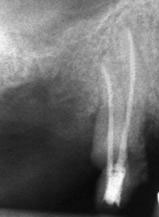

Рентгенографии на добре пролекувани зъби

Винаги е необходимо лекуващият да се стреми към този резултат: